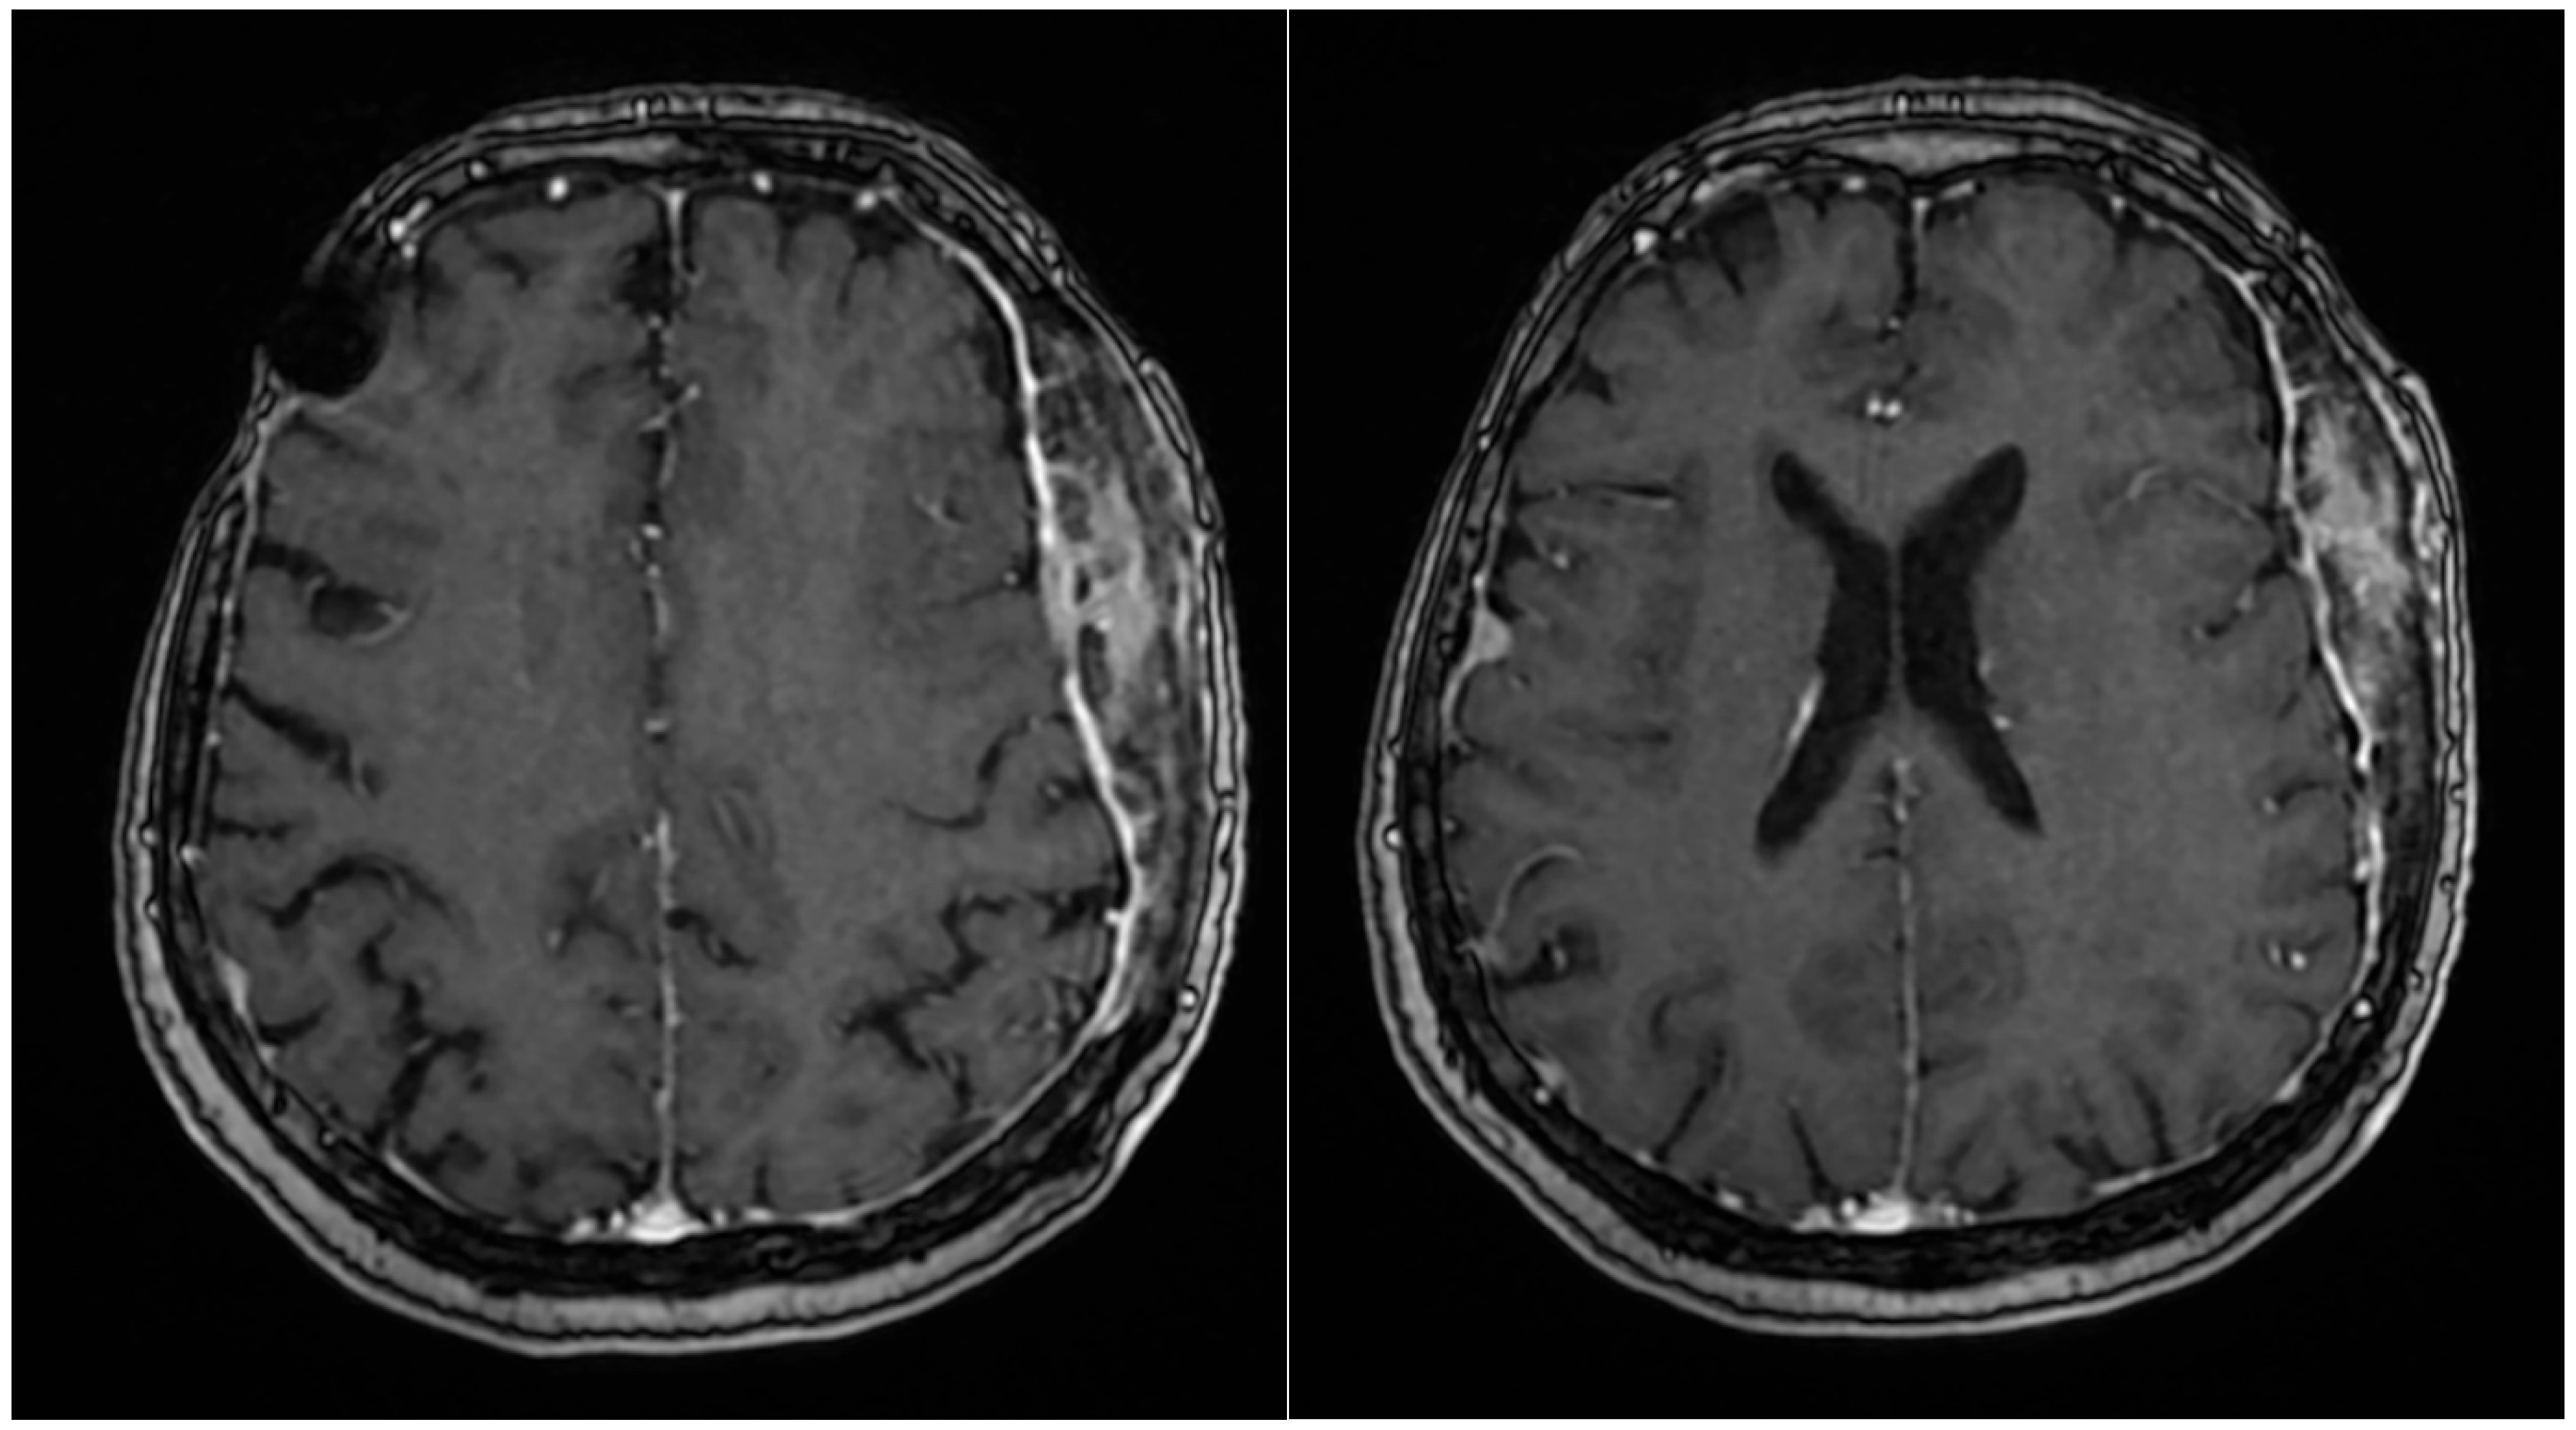

Her 2023 MRI revealed a porencephalic cavity following neurosurgical intervention, which communicated with adjacent cerebral sulci, resulting in secondary widening and perilesional gliotic changes. No contrast enhancement was observed. At the left fronto-temporo-parietal bone, tumor-related changes were noted, characterized by contrast enhancement, bone structural inhomogeneity, and extension both intracranially (extraneuraxial involvement) and into the soft tissues of the scalp. The central osteolytic area measured 49 × 22 × 76 mm (AP × LL × CC) and was surrounded by inhomogeneous osteosclerosis of the adjacent skull. The meninges appeared diffusely thickened with mild irregularities and contrast enhancement. Additionally, discrete edema was observed in the temporal muscle and adjacent fat tissue. The MRI also demonstrated stable findings of multiple right-sided meningiomas (frontal, temporal, and parietal), a left temporal meningioma, and a fronto-temporo-parietal intraosseous meningioma (Figure 1). The magnetic resonance examination was performed on a 1.5 Tesla MRI machine (SignaTM Explorer General Electric, GE Healthcare, Fairfield, Waukesha, WI, USA; MR software release: SV25.2_2127a).

Given her history of multiple meningiomas, a neurosurgery consultation was obtained. MRI revealed no progression of the previously identified meningiomas (Figure 4), and the skin lesion was found to be adjacent to the intraosseous meningioma. Skin ultrasound of the lesion demonstrated soft tissue infiltration consistent with meningiomatosis. Additional investigations, including mammography and a gynecological exam, showed no abnormalities.

Figure 1. MRI examination with iv contrast media, axial 3D T1 FSPGR (14 February 2023). MRI (2023) showing a porencephalic cavity in the left fronto-temporo-parietal region, post-neurosurgical intervention. Tumor-related changes include a large central osteolytic lesion (49 × 22 × 76 mm) with irregular bone structure and soft tissue extension. Surrounding inhomogeneous osteosclerosis, diffuse meningeal thickening, and mild temporal muscle edema are noted. No contrast enhancement is seen in the porencephalic cavity. Stable multiple meningiomas are also present.

Figure 4. The same examination 16 months later revealed the same aspect, without significant changes.